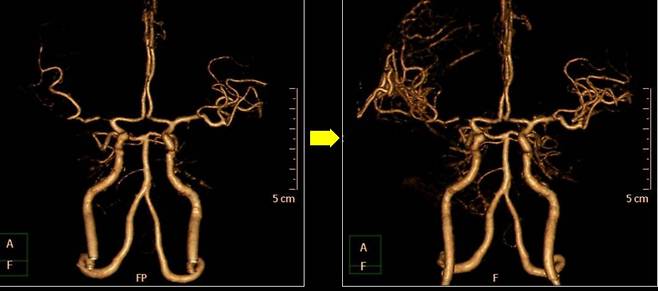

이런 뇌졸중 치료 분야에 '글로벌 강국'이 바로 한국이다. 뇌졸중 급성기 치료는 약물로 막힌 혈전(피떡)을 없애거나 기계적으로 흡입하고, 미세 스텐트를 이용해 빼내는 등 그 폭이 점차 확대되고 있다. 뇌혈관이 막혔는데, 함부로 손댔다가 터질지 모르는 '위험 부위'라면 해당 혈관을 다른 혈관과 이어 우회로를 만들기도 한다(뇌혈관 문합술). 뇌가 부어올라 정상적인 뇌세포를 압박할 땐, 두개골을 떼내어 압력을 낮춘 뒤 3D프린터로 해당 두개골을 '맞춤 재생'하기도 한다.

나아가 뇌졸중이 발생하기 전 예방적인 목적의 치료도 활발히 시행되고 있다. 뇌로 가는 목의 혈관이 좁아지는 경동맥 협착은 풍선과 스텐트를 이용해 뚫거나(혈관 성형술) 직접 혈관을 열어 기름 덩어리인 '플라크'를 제거하는 수술(경동맥 내막 절제술)로 다스린다.

뇌 속 혈관이 부풀어 오르는 '뇌동맥류'도 발견 시 크기, 위험도 등을 고려해 예방적 차원에서 처치할 수 있다. 김문철 병원장은 "부푼 혈관을 클립으로 잡거나 백금 소재의 부드러운 코일을 채워 치료한다"며 "크기가 크고 여러 곳에 생긴 뇌동맥류도 이제는 촘촘한 스텐트 형태의 'WEB'이란 기구를 넣어 혈류를 억제하면 충분히 없앨 수 있다"고 말했다.